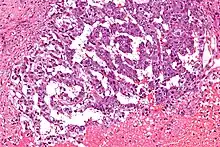

- Sarcoma botryoides